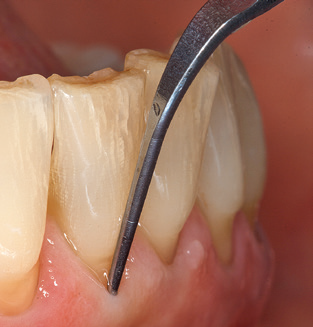

Das aktuelle Arbeitskonzept für die UPT

Die gute Ausleuchtung des Arbeitsfeldes stellt eine wesentliche Erleichterung dar. Bei dem von den Autoren genutzten System ist dies gelungen, indem ein 5facher LEDRing in das Handstück integriert wurde. Natürlich werden für dieses System unterschiedliche Arbeitsspitzen für die jeweiligen Indikationsbereiche angeboten. Eine gerade, universell einsetzbare Spitze ist das Basisinstrument zur maschinellen Instrumentierung natürlicher Zähne (Abb. 5a und b). Für schwer zugängliche Bereiche im Seitenzahnbereich werden gebogene Spitzen angeboten, die auch einen Zugang zu freiliegenden Furkationen ermöglichen (Abb. 6).